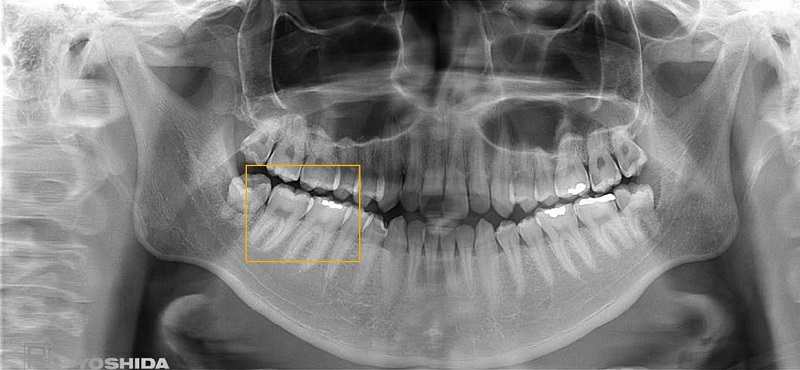

Hình ảnh chụp toàn hàm từ X-ERA Smart